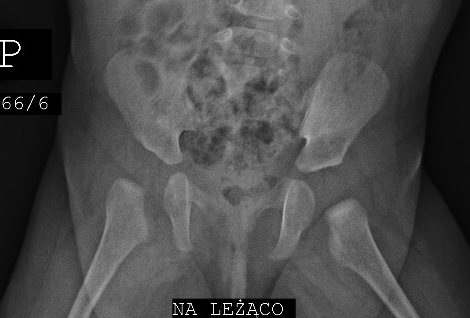

case Barbara 6m after spica cast and two mal traction

after 2 months preventation by eltern